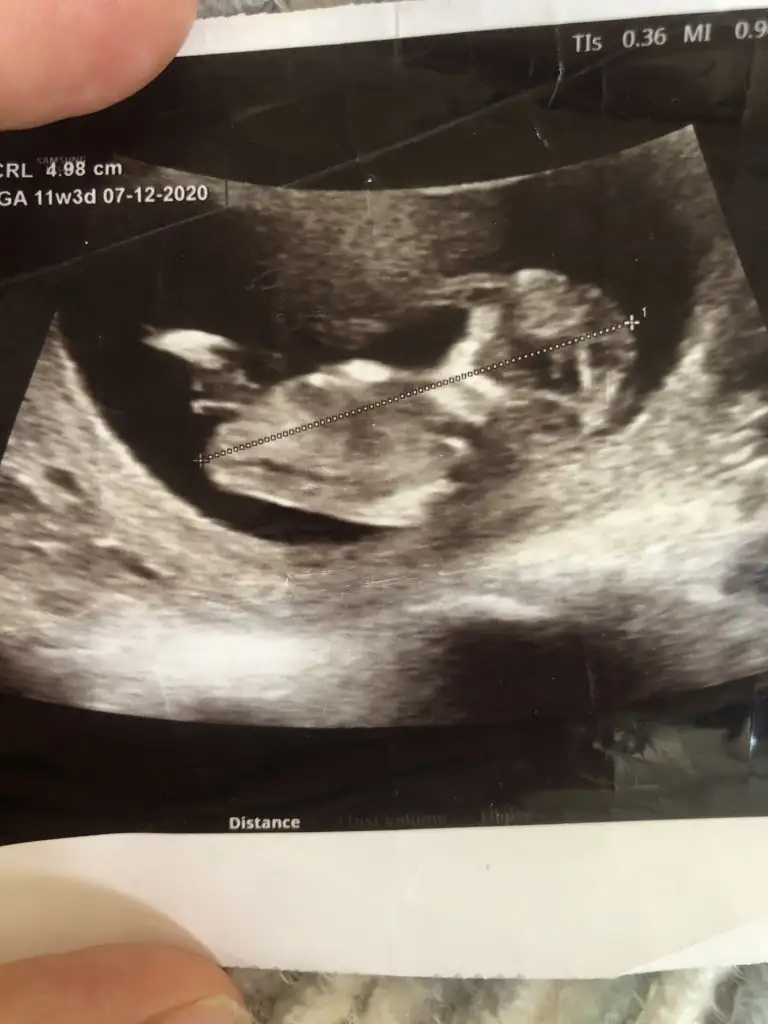

Erkek olabilirKızlar 12 haftalık bizede yorum yapar mısınız?Eki Görüntüle 2643333 Eki Görüntüle 2643334 Eki Görüntüle 2643335

Erkek benceMerhaba bebeğimiz göstermedi bize cinsiyetini donuverdi arkasını 12+3 haftalık bi tahminde bulunabilir misiniz

Teşekkür ederimErkek bence